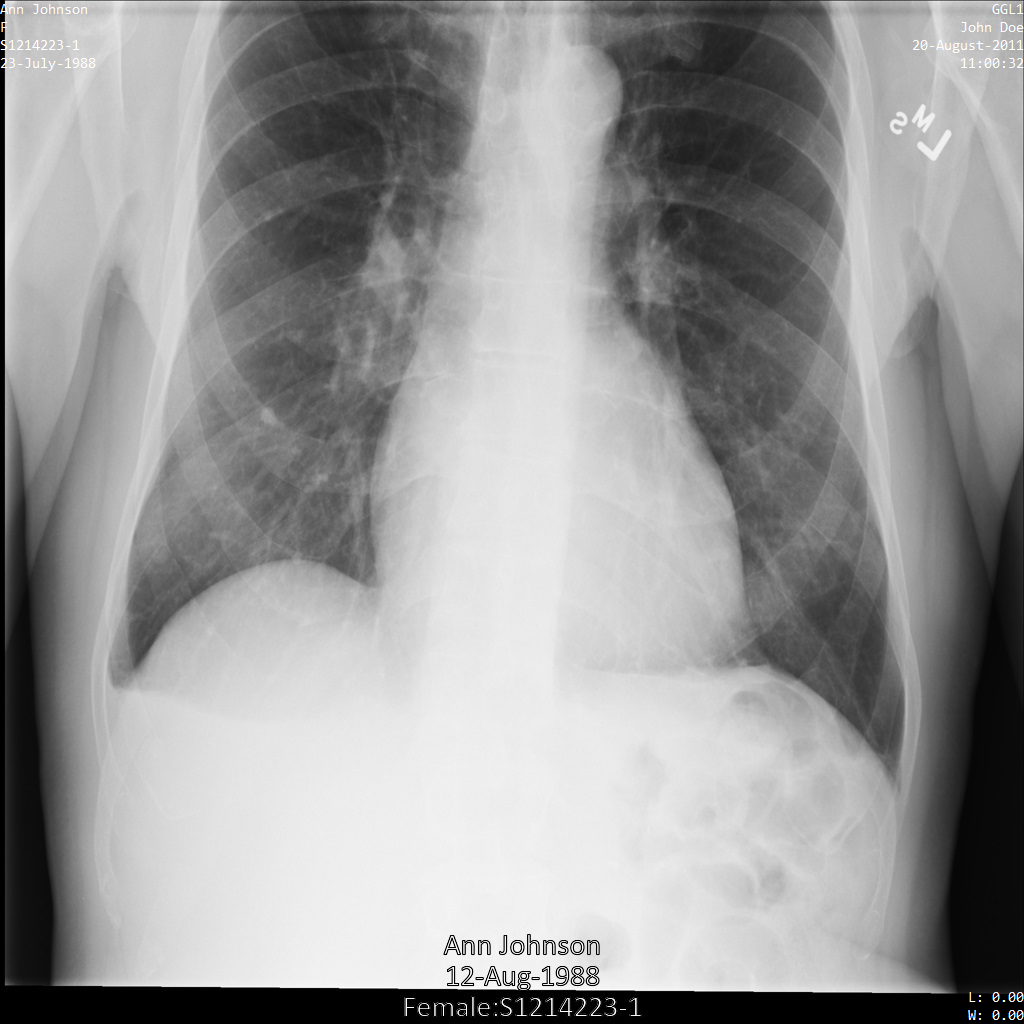

L'image suivante montre une radiographie non masquée d'un patient :

Une fois l'image envoyée à l'API Cloud Healthcare à l'aide de l'option REDACT_SENSITIVE_TEXT, elle apparaît comme suit :

Vous pouvez constater que les événements suivants se sont produits :

- Le paramètre

PERSON_NAMEen bas à gauche de l'image a été masqué. - Le paramètre

DATEen bas à gauche de l'image a été masqué.

Le sexe du patient n'a pas été masqué, car il n'est pas considéré comme du texte sensible selon le paramètre infoTypes DICOM par défaut.